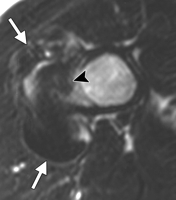

IRM :

- bas signal T1 et T2

- invasion fréquente de la cavité médullaire

* O.P de bas grade 41 %

* O.P de haut grade 50 %

- parfois autre composante associée en hypersignal T2

* si > 1 cm3 alors OP de haut grade